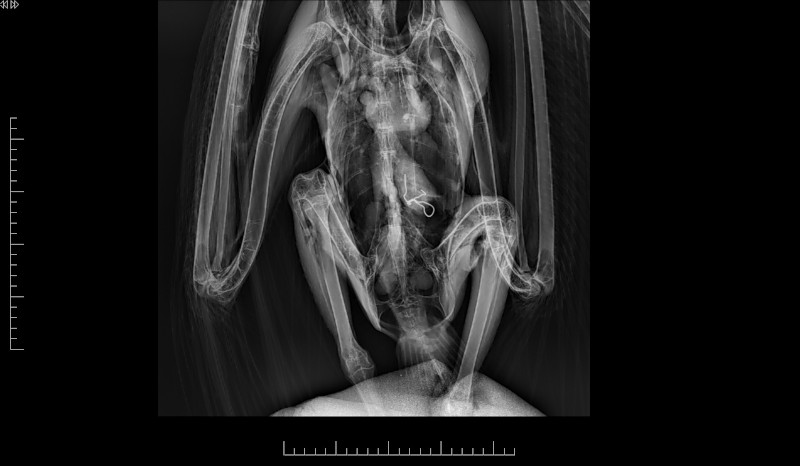

Agentes Forestales de la Comunidad de Madrid rescataron el pasado 2 de septiembre a un buitre leonado que accidentalmente fue a parar al patio de la cárcel de Estremera. El ave fue trasladada al Hospital de Fauna Salvaje de GREFA, donde se le diagnosticó una intoxicación por plomo, deshidratación, hipotermia y bradicardia, además de detectarle un alambre de unos siete centímetros en su aparato digestivo.

El equipo veterinario de GREFA tuvo que intervenir quirúrgicamente de urgencia al buitre leonado rescatado para extraer el alambre, una operación que resultó todo un éxito. Actualmente, el buitre se encuentra en proceso de recuperación en las instalaciones de nuestra ONG conservacionista destinadas a este fin, aunque su evolución dependerá también de cómo responda al tratamiento contra la intoxicación por plomo.

Veterinarios de GREFA operan al buitre leonado para extraerle el alambre.

El buitre leonado rescatado tras la operación y anestesiado en el quirófano de GREFA.